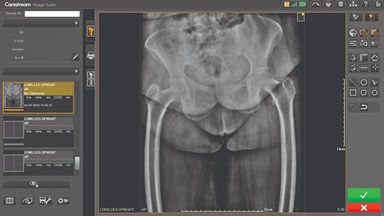

Upgrading your imaging system to a solution designed for outstanding image quality is no longer out of reach — it's now easier, more affordable, and more effective than ever before.

Our Carestream Focus HD 35/43 Retrofit Detectors, powered by Image Suite Software, are an ideal solution to step up to full digital X-ray for customers who simply cannot compromise on image quality. It seamlessly integrates into existing setups, bringing the power of full digital X-ray with minimal disruption and maximum clarity, along with the following benefits: